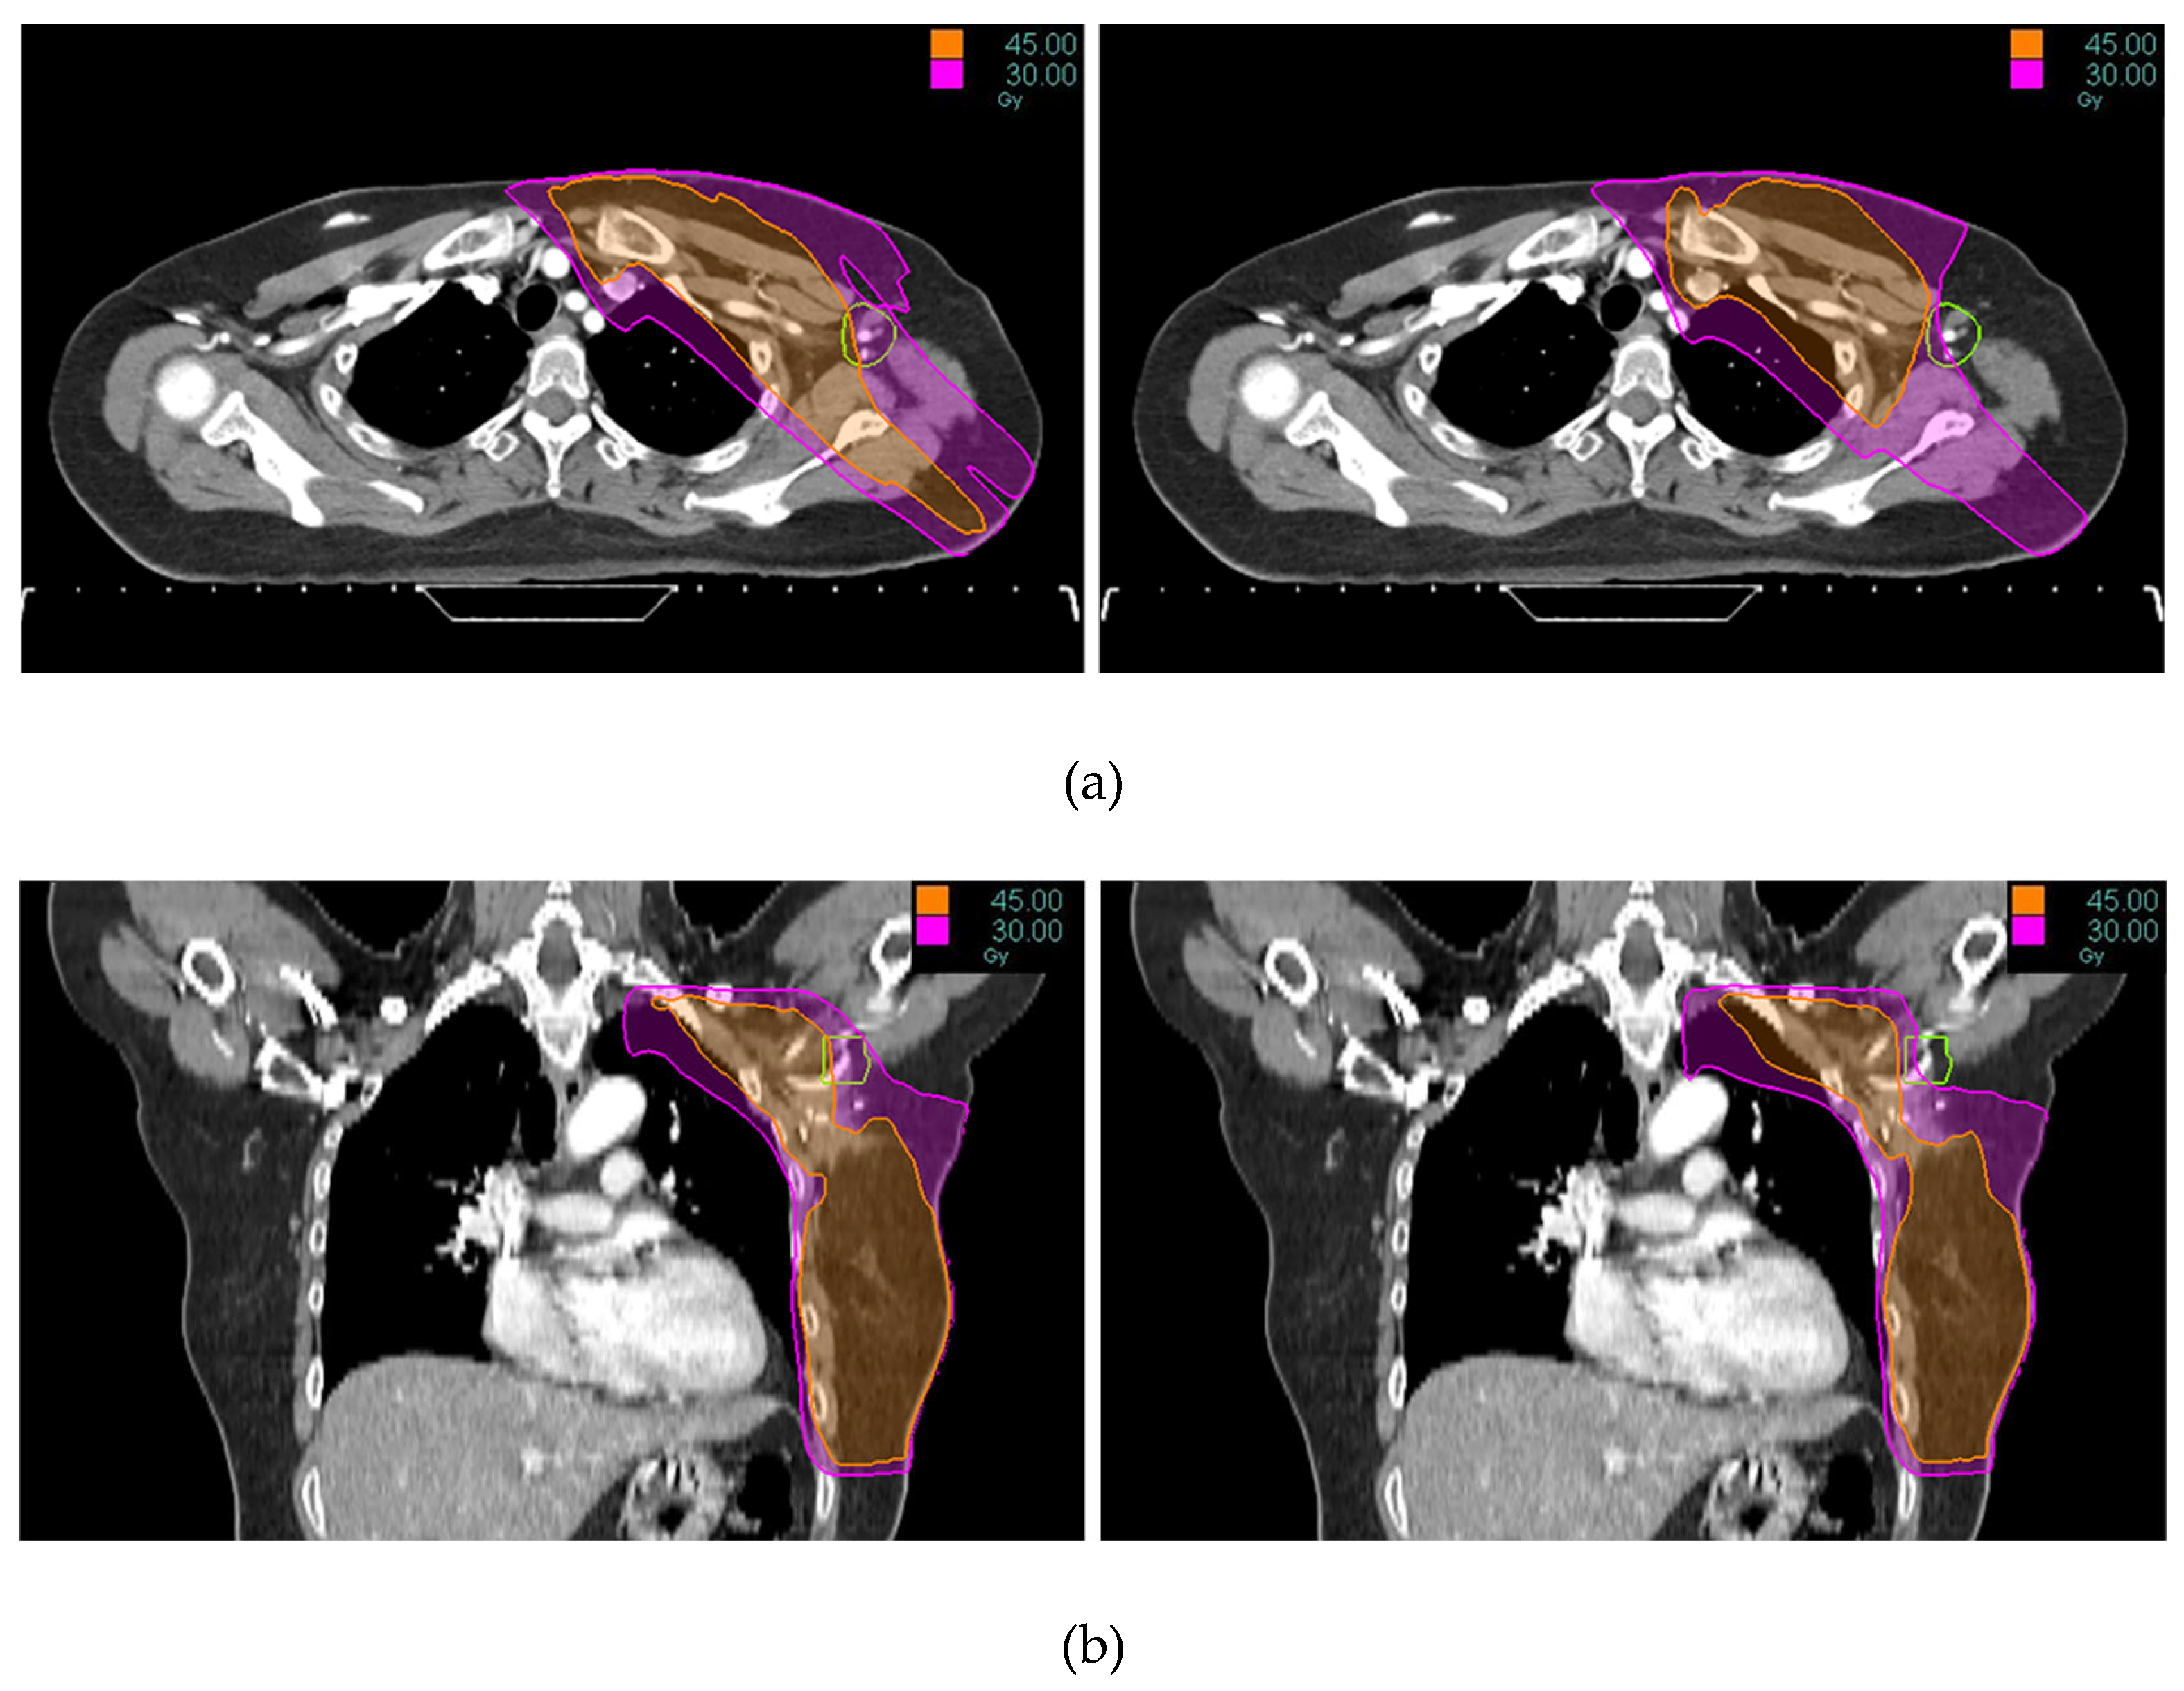

Tomotherapy plan images along with the DVH of a typical patient is illustrated in Figure 1 and Figure 2. The newly generated plans, successfully optimized to meet all standard dose-volume constraints for both target volumes and standard OARs, achieved significant sparing of the ALTJ without compromising the dose received by other critical OARs.

Figure 1. Tomotherapy plan image of a typical patient: (a) axial view, (b) coronal view. The contoured ALTJ (green) is shown, and the dose distributions with isodose lines (30 and 45 Gy) compared between conventional (left) vs. study plan (right).